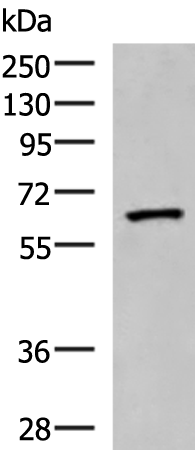

分类: 科研抗体货号: P09880别名: PDIR应用: WB,IHC反应种属: Human, Mouse, Rat